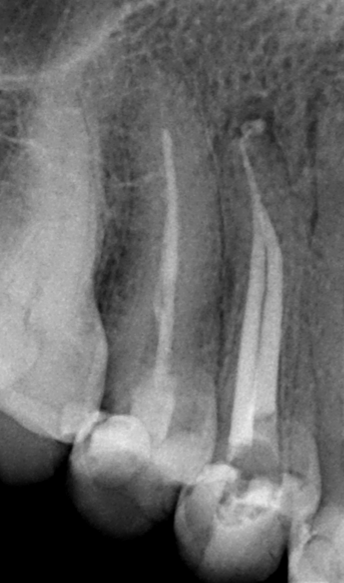

Single session retreatment in upper first premolar with separated instrument in palatal root.

Hugos Case pre xRay

Pre-OP X-Ray

Retreatment of an upper first premolar with a separated instrument in the palatal root.